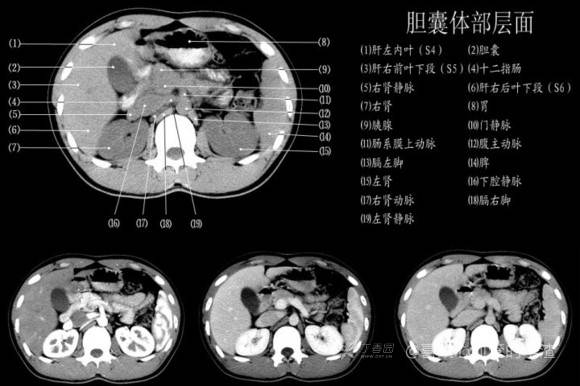

其实你离掌握上腹部 CT 影像只有一套高清实用图谱的距离,下面把我最喜欢的这本图谱分享给大家,为了方便阅读,我加了中文标识。后面附赠几张血管相对位置解剖关系图片,帮助大家理解(文中多图,建议在 wifi 环境下查看)。